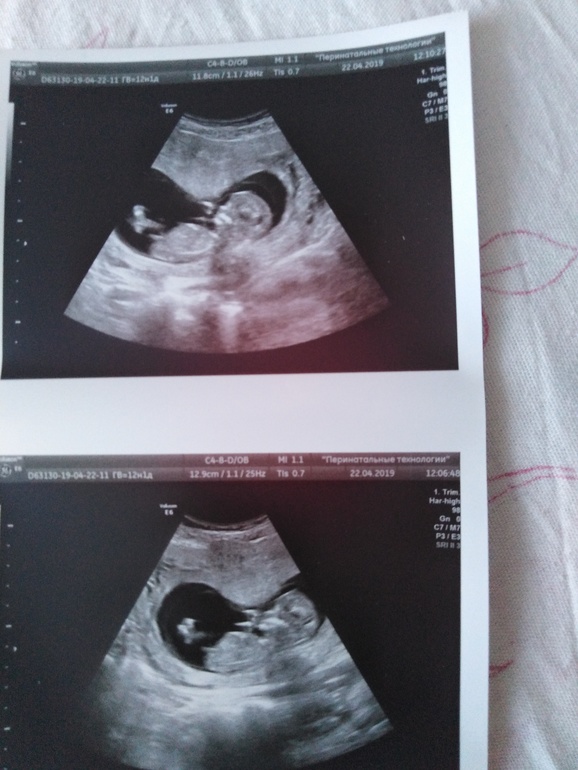

Девочки опытные гляньте по фото... Кто в домике?

Девочка,тк параллельно позвоночнику торчит:)

Я не спрашивала у врача... Знаю что их бесит этот вопрос.. На первом скрининг)) Для меня главными словами было.... Анатомически ребёнок сформирован правильно.. Все её я больше ничего не хотела просто любовалась на его в экране. А сейчас интересно... Видела много постов.. Про глядели по фото... У меня 3 дочи...конечно интересно... Рожу уже парня мужу или нет🤗🤗🤗

Мне на первом скрининге сами предложили пол посмотреть, а я думала, что еще совсем рано. Но они не ошиблись, потом два раза подтвердили, причем я сама никогда не прошу пол посмотреть, а в жк когда шейку смотрели в 16 недель, тоже пол сами сказали. Для сравнения, вот так у нас в 12 недель было

Девочка, половой бугорок не торчит, а почти параллельно